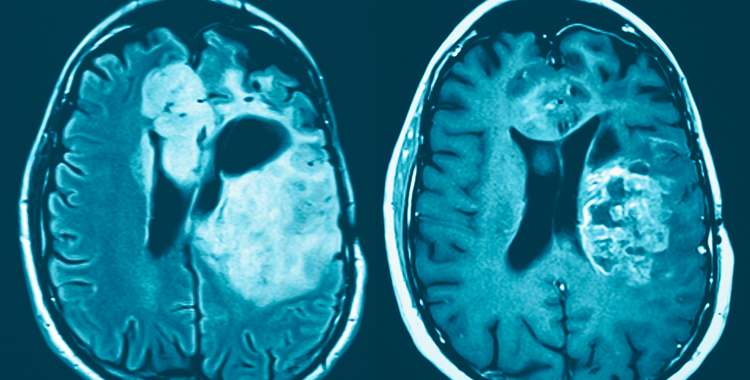

Baggrunden er, at alle, der bliver alvorligt syge, har brug for et støttende netværk, og at specielt mennesker med hjernetumorer og deres familier har særligt behov for social støtte (1). Det hænger sammen med, at mange af patienterne får kognitive eller funktionelle problemer, som påvirker hele familien; forandringer, som let fører til, at de isolerer sig socialt. Samtidig har forskning og erfaring fra Kræftafdelingens ungdomsafsnit gennem 15 år vist, at netværksmøder kan hjælpe den sociale støtte fra netværket på vej og være med til at holde sammen på familiens verden (2,3,4,5).